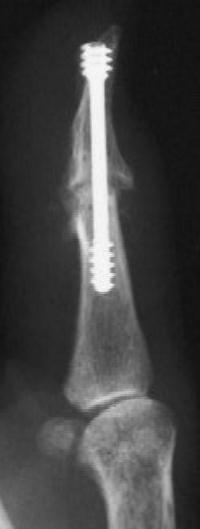

Herbert screw fixation seems most solid if leading threads are in the narrowest segment - the phalangeal neck.